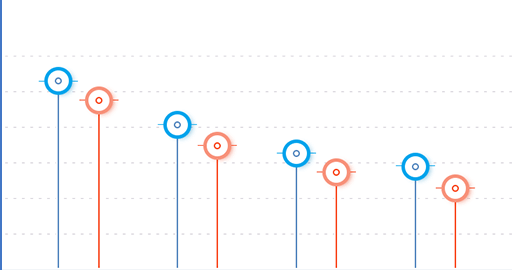

Arnica montana

Má protizápalové účinky

Boswellia Serrata

Chladí pokožku a má lokálne anestetické účinky

Cupressus sempervirens

Má antiseptické a protizápalové vlastnosti.